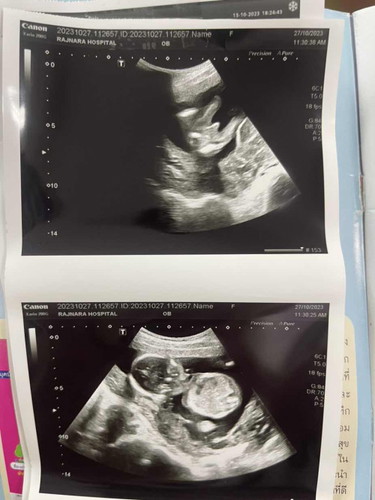

เพศของลูกๆ 😎

ยังต้องลุ้นอีกมั้ยค่ะ ว่าหญิง หรือ ชาย 😂 ท้อง 17 วีคค่ะ

ไม่แน่ใจหญิงหรือชายเอาขาไขว้กันไว้ ลุ้นมากค่ะหมอนัดอีกทีอาทิตย์หน้า อยากได้ลูกสาว☺️☺️

เหมือนกันเลย ผู้ชาย ไม่ต้องลุ้นแล้วคะ แม่ 😄